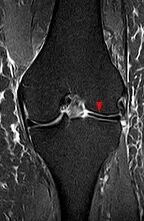

盘状半月板较正常半月板厚度更厚,形状呈椭圆形或圆盘状。根据形状,盘状半月板又分为完全盘状(大盘状)和不完全盘状(小盘状)。盘状半月板常见于膝盖外侧的半月板,内侧很罕见,有时双膝都有。亚洲人群盘状半月板发生率较高。

到底是不是盘状半月板,查个磁共振就很清楚了,磁共振上可以很明显地看出半月板是否为盘状、有无撕裂等情况。

磁共振显示:盘状半月板丨医生供图